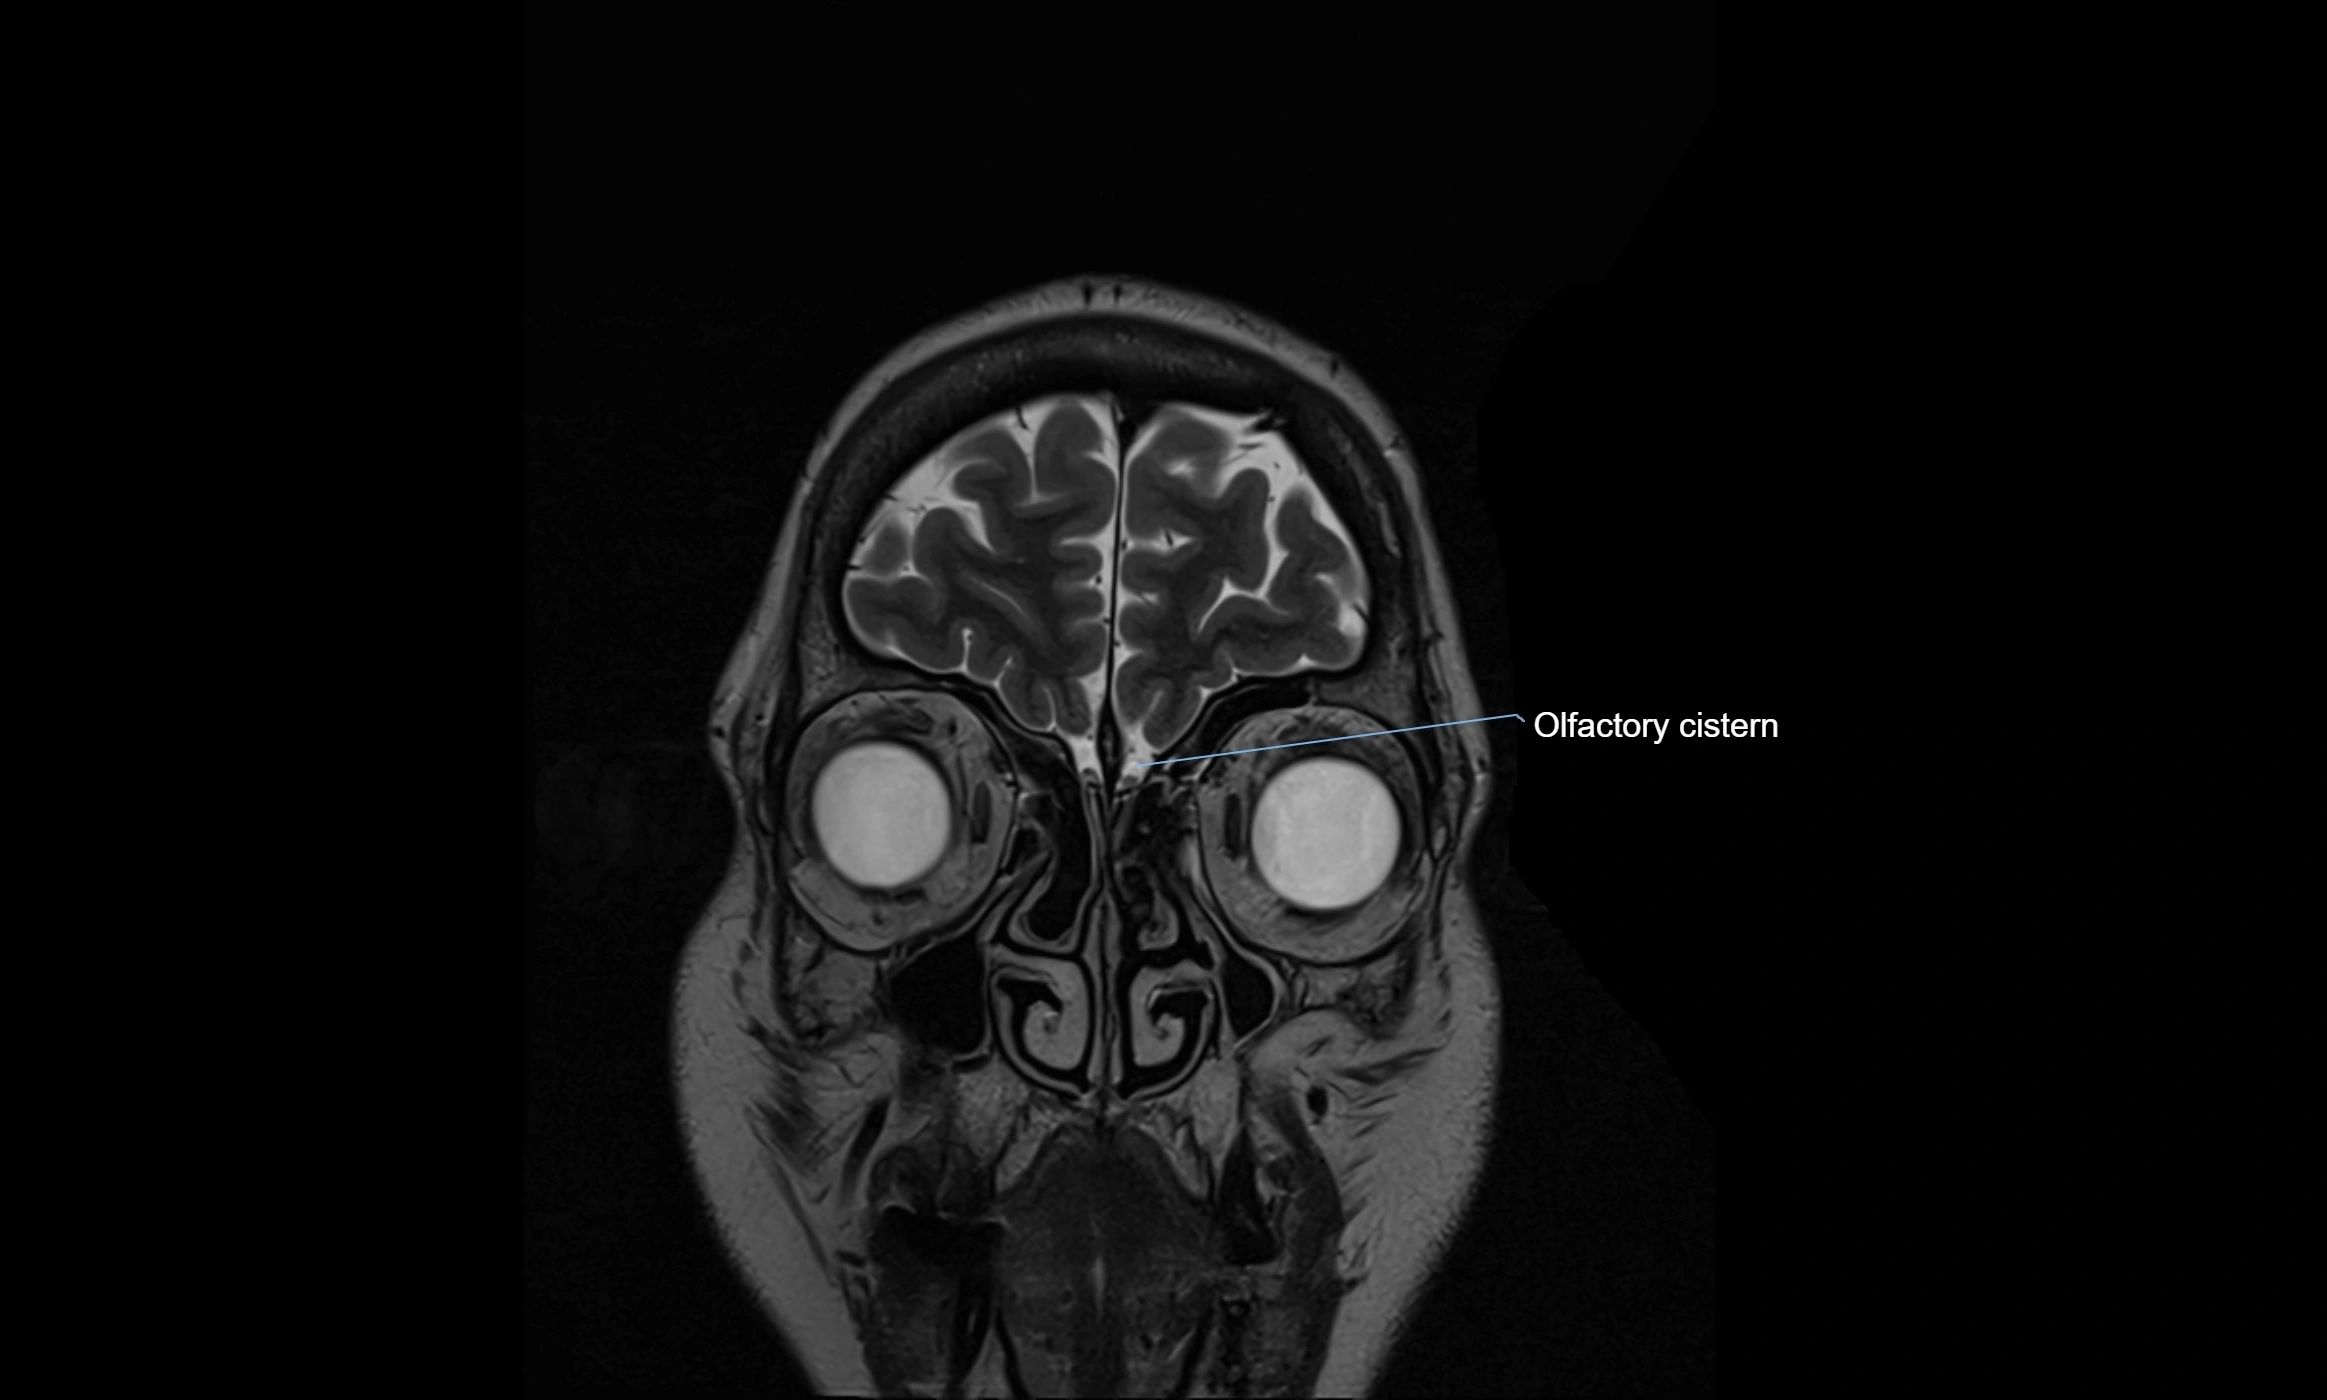

MRI images

image